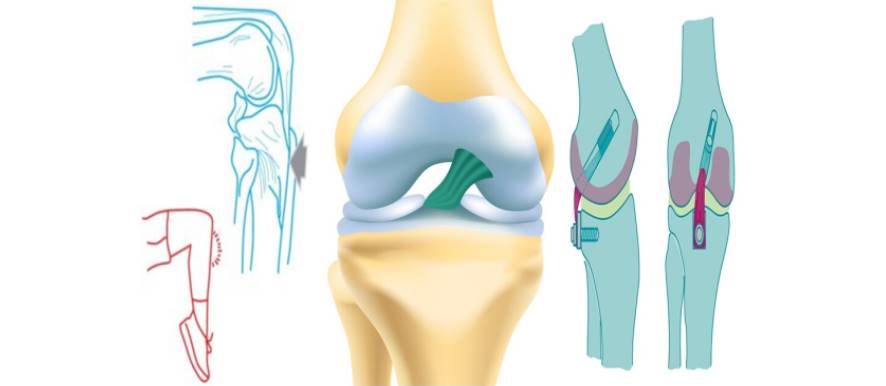

Ο χειρουργός προετοιμάζει την άρθρωση για να δεχθεί το μόσχευμα, διανοίγοντας τις οστικές σήραγγες (μία στο μηρό και μία στη κνήμη).Τα σημεία επιλογής για την καθήλωση του μοσχεύματος εξασφαλίζουν την ανατομική του τοποθέτηση. Μέσα από ειδικά διαμορφωμένες σήραγγες θα περάσει και θα σταθεροποιηθεί το μόσχευμα με ειδικό σύστημα στον μηρό και με απορροφήσιμο κοχλία στη κνήμη.